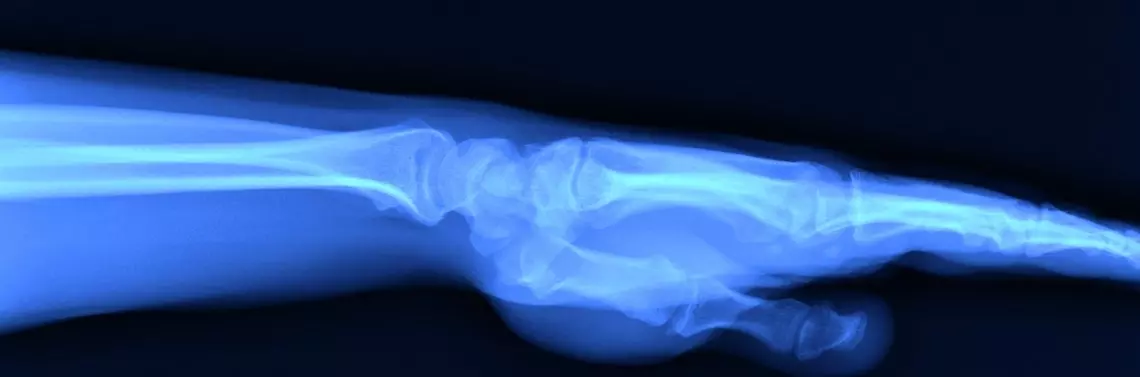

Niekiedy RTG pozwala odkryć również patologie tkanek miękkich w postaci złogów w rzucie przestrzeni podbarkowej – najczęściej są to złogi w kaletce podbarkowej lub w stożku rotatorów w przebiegu wapniejącego zapalenia ścięgien czy entezopatii. W przypadku stawu łokciowego wystarczają 2 projekcje – AP i boczna, ocenia się koncentryczne przyleganie nasad kostnych, szerokość szczeliny promieniowo-ramiennej (norma 2–3 mm), kąt fizjologicznej koślawości (norma ok. 15°) oraz kąt trzonowo-nasadowy (norma ok. 140°) szczególnie ważny u dzieci, gdzie widoczne jest tylko jądro kostnienia bloczka k. ramiennej i wobec zmian tego kąta wnioskuje się o złamaniu nadkłykciowym k. ramiennej. W przypadku nadgarstka stosuje się 2 podstawowe projekcje (AP i boczną) oraz kilka dodatkowych – skośne dla k. łódeczkowatej, w odwiedzeniu promieniowym i łokciowym oraz w pozycji zaciśniętej pięści (zdj. 4).

W projekcji AP w warunkach prawidłowych k. promieniowa jest dłuższa niż łokciowa, a przestrzeń będąca różnicą wymiarów zajęta jest przez TFCC. Dalsze nasady tych kości przylegają do siebie lub tworzą szczelinę maksymalnie 1 mm, podobnie jak kości łódeczkowata i księżycowata, przy czym ta ostatnia szczelina nie powiększa się w odwiedzeniu ani w pozycji ściskania pięści. Kąt nasadowy k. promieniowej wynosi ok. 20°. W projekcji bocznej kąt nasadowy k. promieniowej wynosi 10° i jest skierowany w kierunku dłoniowym, a kąt pomiędzy k. łódeczkowatą i księżycowatą powinien się mieścić w szerokich granicach normy 30–60°. Metodą przeznaczoną do oceny struktur kostnych, a przede wszystkim do oceny powierzchni stawowych jest CT. Dzięki badaniu warstw wspartym często rekonstrukcją 3D możliwa jest precyzyjna ocena uszkodzeń powierzchni i wewnętrznych stref kości, lokalizacja odłamów, stopień kompresji powierzchni stawowych, a nawet ocena stopnia ryzyka martwicy pourazowej. Badanie to zapewnia bardzo dobre planowanie przedoperacyjne w rekonstrukcjach po urazach, a także przy planowaniu resekcji zmian nowotworowych (zdj. 5).